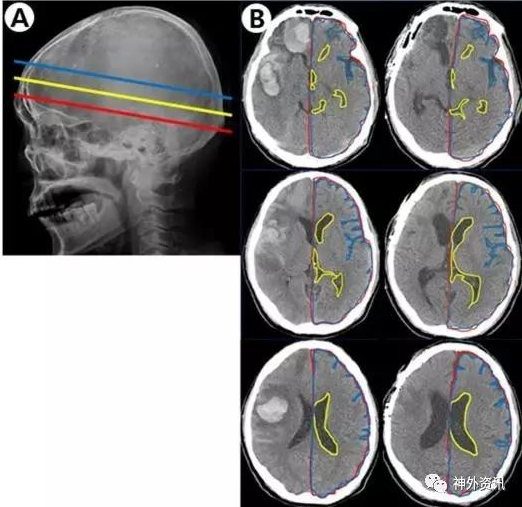

该研究收集作者所在单位2011年至2015年接受手术治疗的自发性脑出血患者。研究对象的血肿位于幕上单侧大脑半球;根据术前和术后3个月在头颅CT轴位3个平面,即室间孔平面、透明隔平面和侧脑室平面上的影像片(图1)

计算发生出血对侧的脑实质面积与同侧颅腔面积之比以消除个体差异,分析与对侧脑组织体积变化的相关因素。

总共纳入44例患者,其中12例血肿清除后骨瓣复位,15例行血肿清除加去骨瓣减压术,17例行血肿穿刺引流术。结果表明,所有患者术前与术后3个月CT图像上,在室间孔、透明隔和侧脑室3个平面的对侧脑组织与同侧颅腔面积平均比值,分别为92.3%比88.8%、90.3%比85.3%和86.9%比82.5%,差异均有统计学意义(P<0.001)。血肿破入脑室是导致对侧脑组织体积缩小的最显著因素(P=0.006);此外,入院时GCS评分低(P=0.016)和吸烟(0.039)也是对侧脑组织体积缩小的独立影响因素。